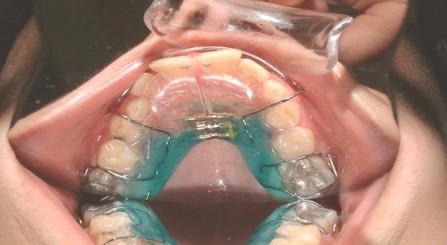

Αν δεν υπάρχει αρκετός χώρος για αυτά,κάνουμε διεύρυνση της υπερώας με ορθοπεδικό μηχάνημα.

024 Με

τον τρόπο αυτό τα βοηθάμε

Από την ορθοδοντική ματιά πρέπει να διαγιγνώσκεται η στοματική αναπνοή, να παραπέμπεται στους ειδικούς γιατρούς και να διευρύνεται η άνω γνάθος με ορθοπεδικούς μηχανισμούς.

Πριν Μετά Η σημασία της στοματικής υγιεινής και ορθοδοντικής πρόληψης

Ορθοδοντική θεραπεία σε παιδί με στοματική αναπνοή. Έγινε διεύρυνση υπερώας. Με τη διεύρυνση της άνω γνάθου, βοηθάμε τα παιδιά προσχολικής και σχολικής ηλικίας να θεραπευθούν σε μεγάλο βαθμό με τη συμβολή φυσικά των παιδιάτρων και ΩΡΛ.